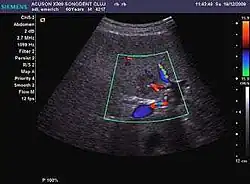

Hepatic hemangioma (2D). The lesion is located in the left hepatic lobe. Note precise delineation, their increased echogenity and the heterogeneous internal structure.

It is the most common liver tumor with a prevalence of 0.4 – 7.4%. It is generally asymptomatic but also can be associated with pain complaints or cytopenia and/or anemia when it is very bulky. It is unique or paucilocular. It can be associated with other types of benign liver tumors. Characteristic 2D ultrasound appearance is that of a very well defined lesion, with sizes of 2–3 cm or less, showing increased echogenity and, when located in contact with the diaphragm, a "mirror image" phenomenon can be seen. When palpating the liver with the transducer the hemangioma is compressible sending reverberations backwards. Doppler exploration reveals no circulatory signal due to very slow flow speed. CEUS investigation has real diagnosis value due to the typical behavior of progressive CA enhancement of the tumor from the periphery towards the center. The enhancement is slow, during several minutes, depending on the size of hemangioma and on the presence (or absence) of internal thrombosis. During late (sinusoidal) phase, if totally "filled" with CA, hemangioma appears isoechoic to the liver. Deviations from the above described behavior can occur in arterialized hemangiomas or those containing arterio-venous shunts. In these cases, differentiation from a malignant tumor is difficult and requires other imaging procedures, follow up and measurements of the tumor at short time intervals.[4]